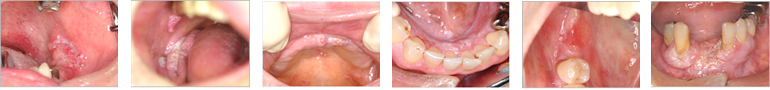

●口腔がんの症例写真

舌がん

舌がん(舌にできるがん)は口腔がんの中でも最も多いがんです。そのほとんどで、舌縁部(舌の側面)や舌の裏側にでき、舌の上面にできることはほとんどありません。

粘膜面が、赤くなったり、白くなったり、表面が凸凹したり、潰瘍ができたりします。 触ってみて、何か粘膜の下に「かたまり」や厚みのある部分を触れたら要注意です。

虫歯や、歯ならびの悪い歯などで擦れるなどの機械的刺激が原因となる場合も少なくありませんので、その様な歯がある場合や合わない入れ歯やさし歯はきちんと治しておくことが大切です。

開業医だから発見できる口腔がん そのサインの見つけ方と対処法より引用

歯肉がん

歯の生えている部分の粘膜を歯肉と言います。この部分の粘膜が赤くなったり、白くなったり、表面が凸凹したり、潰瘍ができたりします。

歯周病でもないのに、「歯がぐらぐらしてきた」や「腫れてきた」、「歯を抜いた後がなかなか治らない」などの症状のこともあります。歯ぐきの表側ではなく裏側にできることも多いので要注意です。

頬粘膜がん

いわゆる頬の内側、口の中の粘膜に出来るがんです。噛んだり、傷つけた覚えがないのに、粘膜面が、赤くなったり、白くなったり、表面が凸凹したり、潰瘍ができたりします。触ってみて、何か粘膜の下に「かたまり」や厚みのある部分を触れたら要注意です。親知らずの生える部分の粘膜部分も後発部位の一つです。